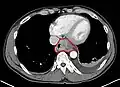

Speziell im Fall eines 3D-Datensatzes werden häufig Schnittbilder oder Schnittbildserien des Körpers errechnet. Die Orientierung der Schnittbildebene und die Position sind dabei meist frei wählbar. Im Gegensatz zu einem Projektionsverfahren wie der Durchstrahlung eines Körpers können so gezielt Details oberhalb oder unterhalb der interessierenden Schicht ausgeblendet werden. Im unteren Beispiel wurde durch die Technik der Schnittebene die störende Information der Rippen entfernt. Teilweise werden für die Diagnose oder Auswertung auch 3D-Rekonstruktionen erstellt, die sich beliebig im Raum orientieren lassen und Anblicke von allen Seiten erlauben.

transversales Schnittbild des Körpers